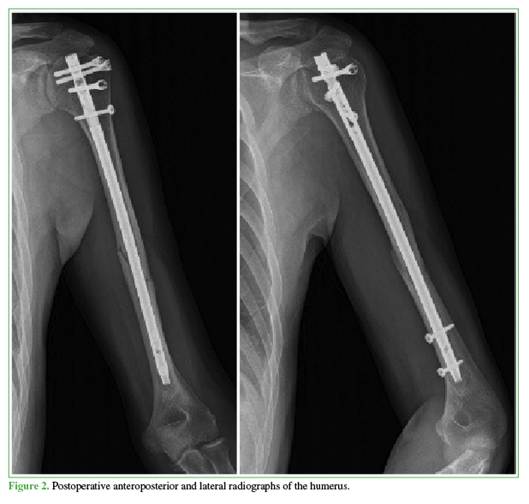

All patients were initially immobilized with a Vietnam sling for two weeks. Wrist pronosupination and wrist/ elbow flexion-extension exercises were initiated 24 hours after surgery. Assisted pendulum exercises using the contralateral limb began during the second week. Active shoulder mobility was started in the third week. Unrestricted anti-gravity activity was permitted six weeks postoperatively, and weight-bearing activities and strengthening exercises were introduced at 12 weeks. Mean clinical and radiographic follow-up was 18 months (range 12–24). Radiographs were obtained immediately postoperatively, at 15 and 45 days, and at 3, 6, 12, and 18 months (Figure 2).